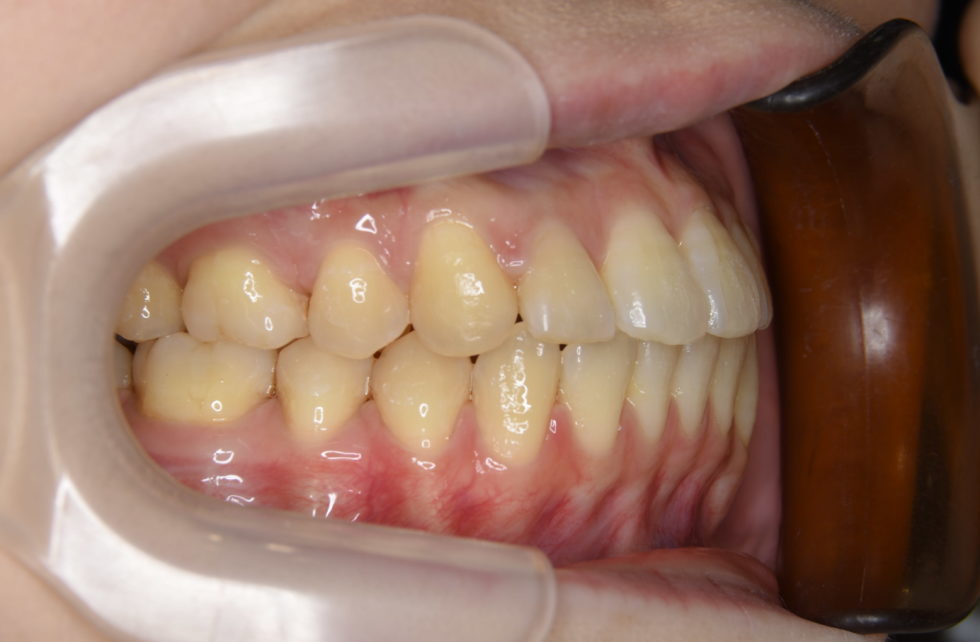

初診時年齢25歳の女性 反対咬合を主訴として来院された。

顔貌はオトガイ部の突出と中顔面の陥凹感があり、口腔内は反対咬合となっていた。比較的強い骨格性反対咬合で、顎離断術を併用した外科矯正の適応であると診断した。上顎左右側第二小臼歯を抜歯していただき顎離断術の術前、術後の矯正治療を行い良好な結果が得られた。治療期間は顎離断術による入院期間を含め3年6か月間